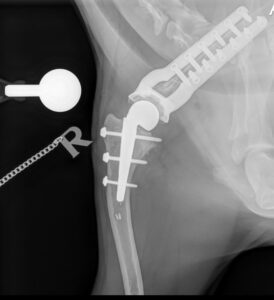

Professor Noel Fitzpatrick replaced the entire deformed shoulder joint with a custom-made implant system created from a CT scan. The construct comprised a large ball anchored on a stem in the humerus, a metal shell anchored to the shoulder blade (scapula) using plates, and a plastic cup liner.

A graphic sequence of Gylly’s total shoulder replacement surgery